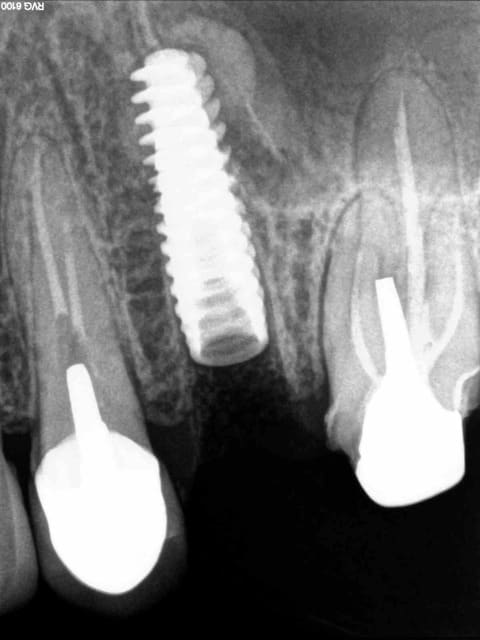

ce matin, extraction et implantation immédiate sur une 25. j'ai prévenue la patiente qu'en cas de stabilité primaire médiocre, je ne prendrai aucun risque et que je ne ferai pas de mise en esthétique immédiate (couronne provisoire).

ce qui devait arriver arriva, ...

désolé madame machin, mais je ne préfère pas mettre de couronne immédiatement, la moitié apical de l'implant est trop instable. (technique de summers)

oh zut alors! et si je vous promets que je ne mangerai pas dessus ?